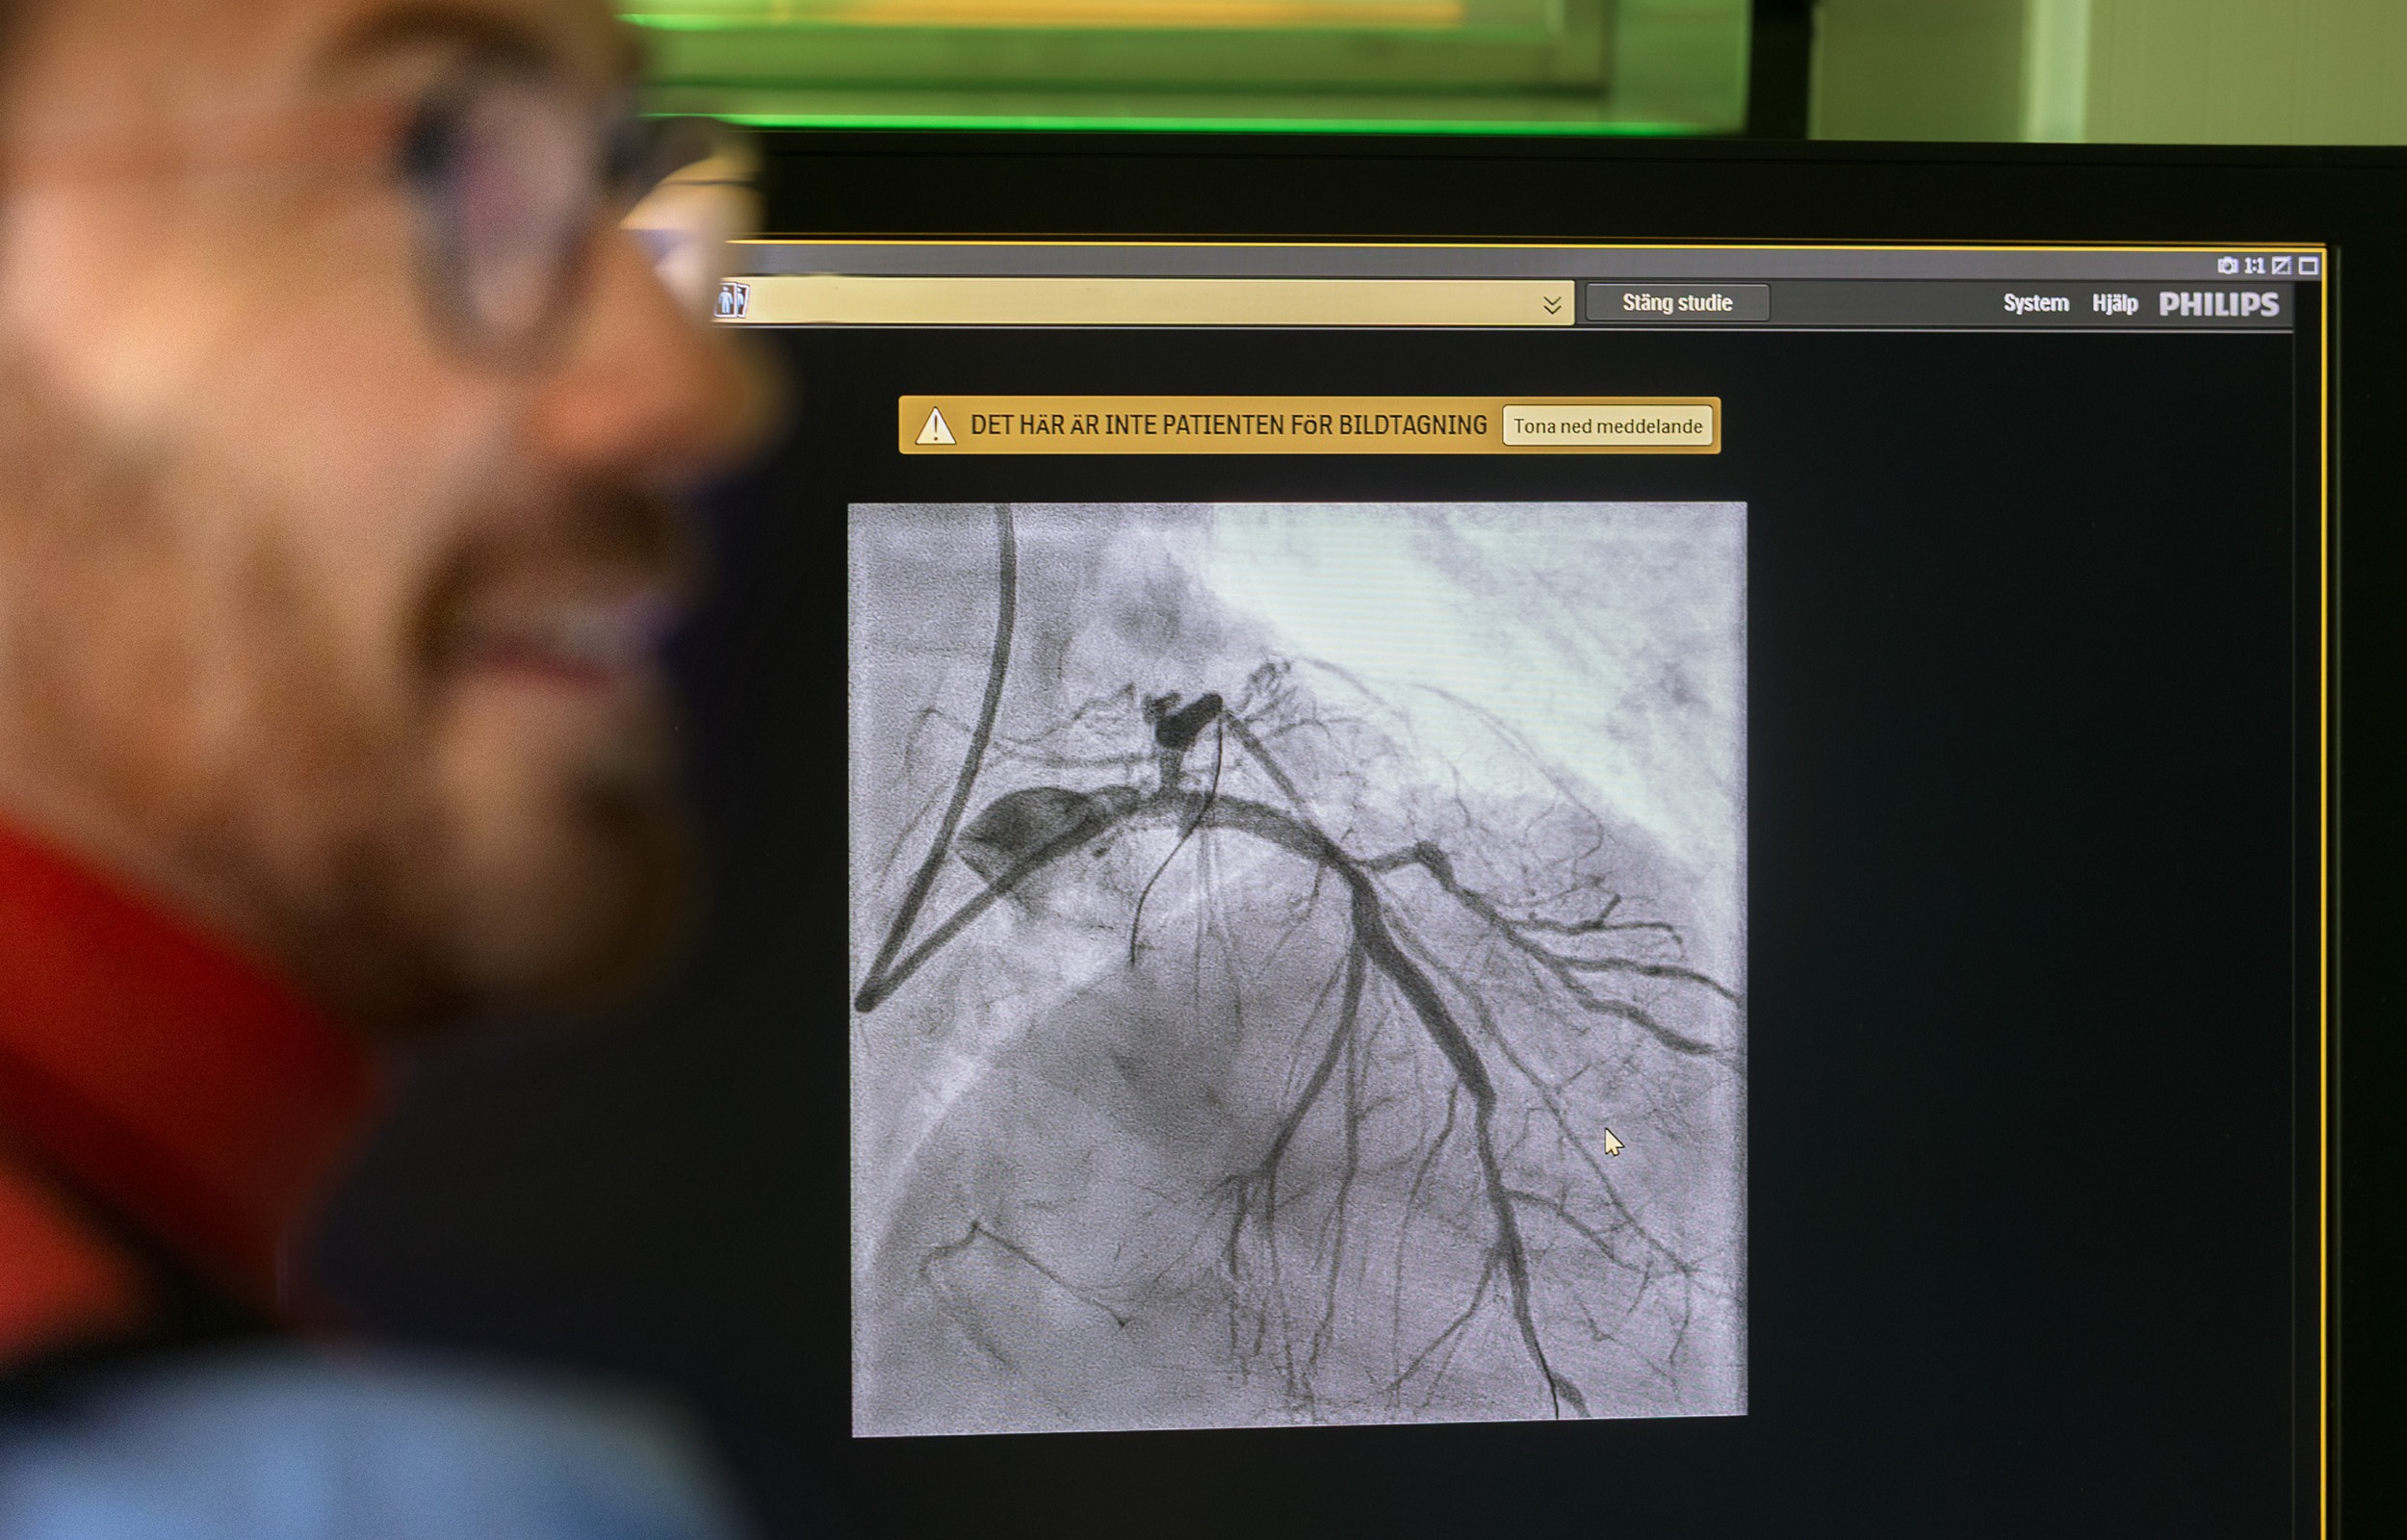

När patienten nått sjukhuset görs en kranskärlsröntgen för att läkarna ska se var proppen sitter. När den är lokaliserad inleder man i samma ingrepp en ballongvidgning (PCI) för att öppna det igensatta blodkärlet.

Läkaren för en tunn kateter via ett blodkärl i handleden eller ljumsken upp till hjärtat. I kateterns spets sitter en liten ballong. När ballongen når det tilltäppta området i kranskärlet blåses den upp – då trycks proppen och den trånga kärlväggen ut så att blodet kan flöda fritt igen. Sedan sätter operatören in ett stent, ett litet nätrör, som håller kärlet öppet.